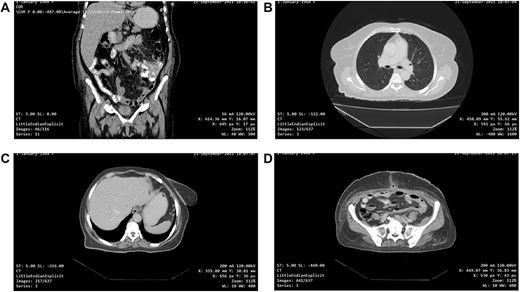

(A and B) CT scan of the abdomen and pelvis demonstrated a large pelvic mass adherent to the sigmoid colon and compressing its surrounding structures.

Tumour arising from the sigmoid colon, adherent to the small bowel and measured 12 × 13 × 16 cm.

Abdominal ultrasound revealed a bulky hypoechoic pelvic mass with ill-defined borders. Computed tomography (CT) scan of abdomen and pelvis established a large pelvic mass adherent to the sigmoid colon and compressing its surrounding organs measuring approximately 10 × 11 × 13 cm. (Fig. 1A and B). Initial management included intravenous fluid resuscitation, analgesics and prophylactic antibiotics.

One-month post-operative computed tomography (CT) scan of the chest/abdomen/pelvis revealed: clear lung fields free of metastasis/lymphadenopathy, liver free of metastasis, no retroperitoneal/pelvic lymphadenopathy, no fluid levels near the surgical intervention field, no masses or signs of relapse/recurrence, and kidneys/spleen/genitourinary system are normal (Fig. 6A–D).

(A, B, C and D) One-month post-operative CT scan of the chest/abdomen/pelvis revealing a coronal view of the abdomen and pelvis/lung/liver/surgical site/pelvis free of tumour spread/metastasis/relapse.